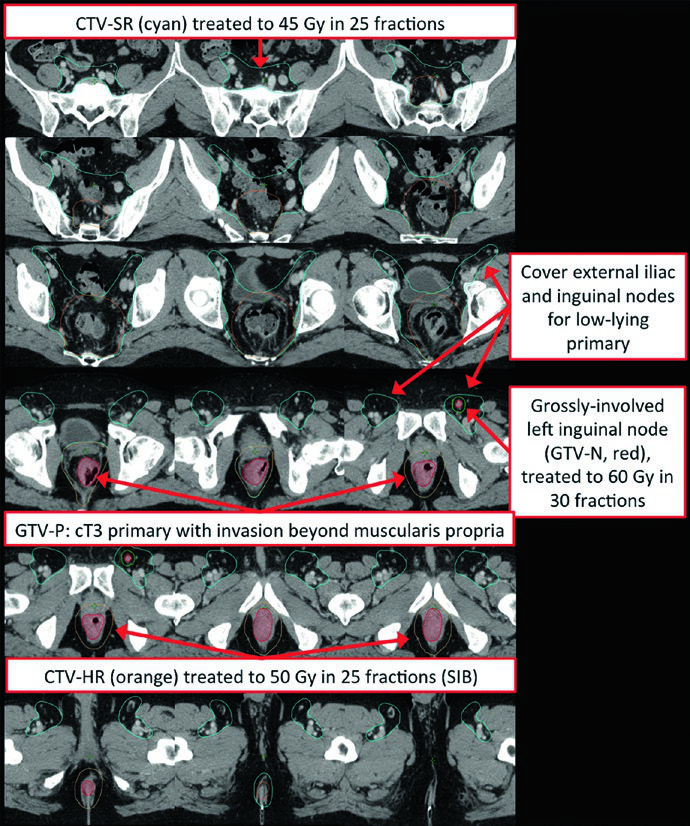

Definição dos Volumes de Tratamento: GTV, CTV-HR e CTV-SR

O GTV primário (GTV-P) engloba toda a doença macroscópica identificada no exame físico, endoscopia e exames de imagem. O GTV nodal (GTV-N) inclui todos os linfonodos perirretais, messorretais e ilíacos comprometidos. Na ausência de biópsia, linfonodos duvidosos devem ser incluídos como GTV. Tumores retais baixos exigem atenção aos linfonodos inguinais, e tumores com invasão anterior em órgãos adjacentes requerem avaliação dos linfonodos ilíacos externos.

O CTV de alto risco (CTV-HR) deve incluir o GTV com margem mínima de 1,5 a 2 cm superior e inferiormente, além de todo o reto, mesorreto e espaço pré-sacral. Para linfonodos ilíacos externos ou inguinais macroscopicamente comprometidos, a margem GTV-para-CTV deve ser de no mínimo 10 a 15 mm. Em tumores T4, adiciona-se margem de 1 a 2 cm nos órgãos adjacentes invadidos (bexiga, próstata, cérvix).

O CTV de risco padrão (CTV-SR) cobre o CTV-HR completo, todo o mesorreto e os linfonodos ilíacos internos bilaterais. A inclusão dos linfonodos ilíacos externos e obturadores bilaterais é obrigatória para tumores T4 com envolvimento de órgãos anteriores (bexiga, cérvix, próstata). Se o tumor primário se estende inferiormente para o canal anal, os linfonodos ilíacos externos e inguinais bilaterais devem ser incorporados ao CTV-SR.

Tumores retais baixos com envolvimento do canal anal representam um desafio particular. Nesses casos, a cobertura inguinal bilateral se torna obrigatória, e o uso de IMRT é frequentemente necessário para atingir conformidade adequada cobrindo os linfonodos ilíacos externos e inguinais bilaterais. A relação entre o delineamento do câncer anal e o câncer retal baixo merece atenção especial, já que compartilham muitas das mesmas regiões de drenagem nodal.

Existem múltiplas abordagens aceitáveis para a prescrição de dose no câncer retal. No cenário pré-operatório, a dose mais comum é de 45 Gy a 1,8 Gy/fração para o PTV-SR, seguida de cone-down sequencial de 5,4 Gy a 1,8 Gy/fração, totalizando 50,4 Gy para o PTV-HR. Tumores T4 podem receber boost no PTV-HR até 54 a 55,8 Gy em 30 a 31 frações. Linfonodos macroscopicamente comprometidos que não serão ressecados (por exemplo, inguinais) devem receber boost até aproximadamente 60 Gy em 30 frações, enquanto linfonodos que serão ressecados podem ser tratados com 50,4 Gy.